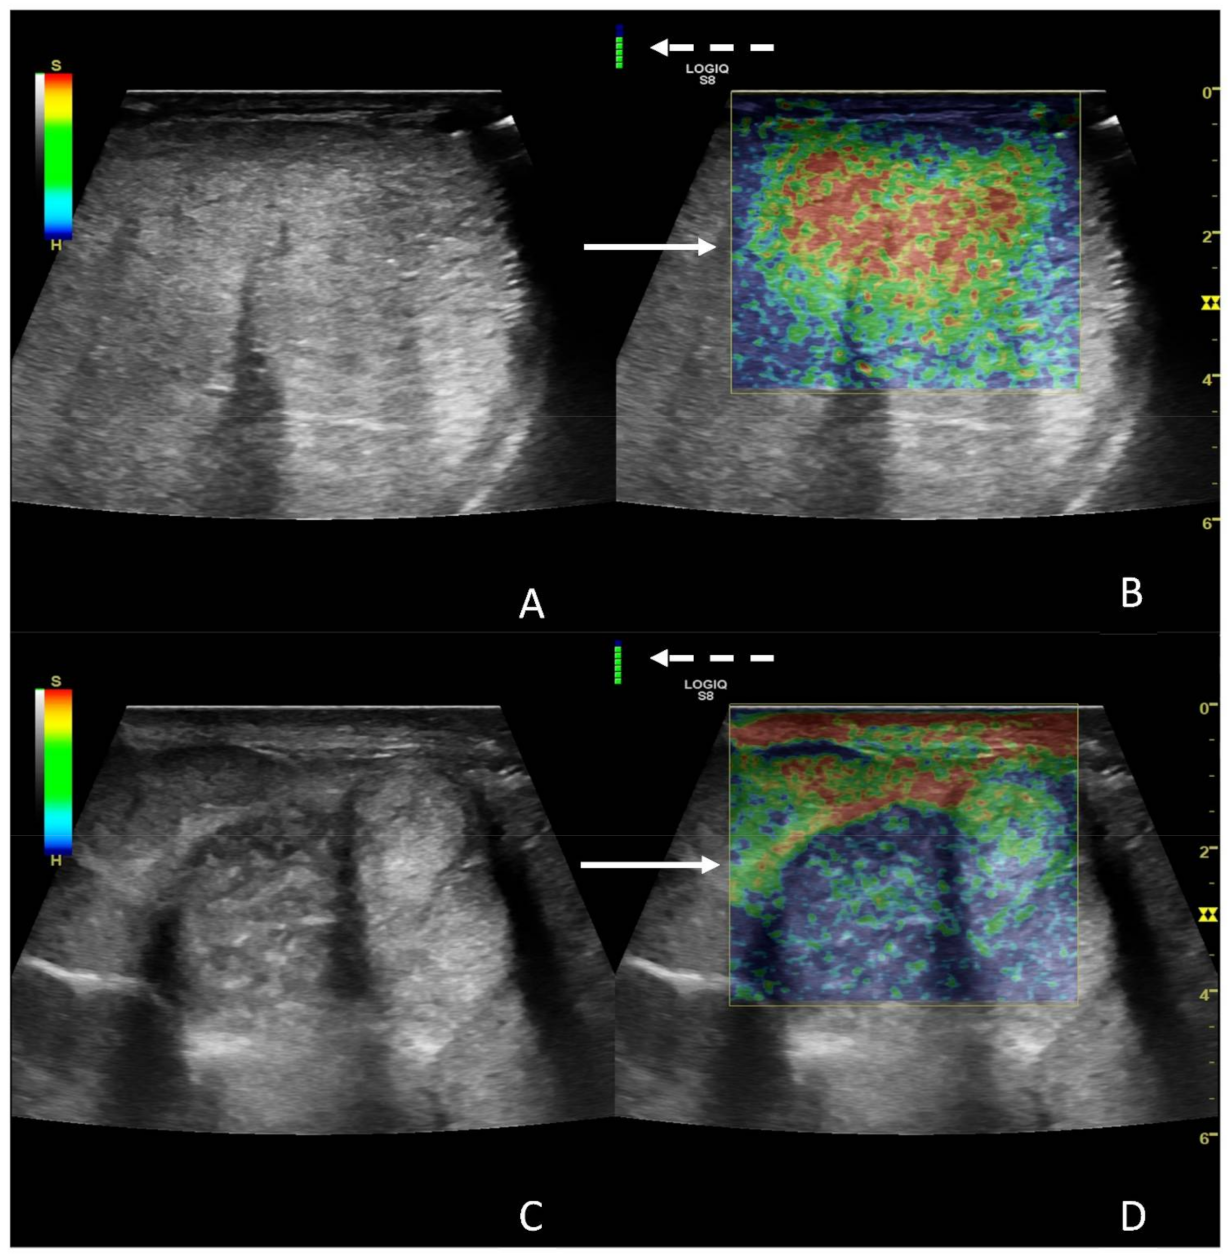

The right testicle was characterized using central parenchymal red-green color with blue edges and without red bands (Figure 5A,B), while the left one was characterized by a heterogeneous appearance, predominantly classifiable as 5, mostly in the central areas, with some areas with 1 and 2 scores localized more peripherally (Figure 5C,D).

Figure 5. Images from SE of a normal (A,B) and a diseased testicle (C,D). In panel A and B, the B-mode image and the elastogram are presented, respectively; in the elastogram, notice the color distribution, characterized by central parenchymal red-green color with blue edges (white solid arrow). In panels C and D, B-mode image and elastogram are presented as well, with the elastogram characterized by an heterogenous pattern, mostly blue with a central small green areas (score 5—white solid arrow). The white dotted arrows point at a color bar is indicative of the quality of examination, which is considered good if it appears green.